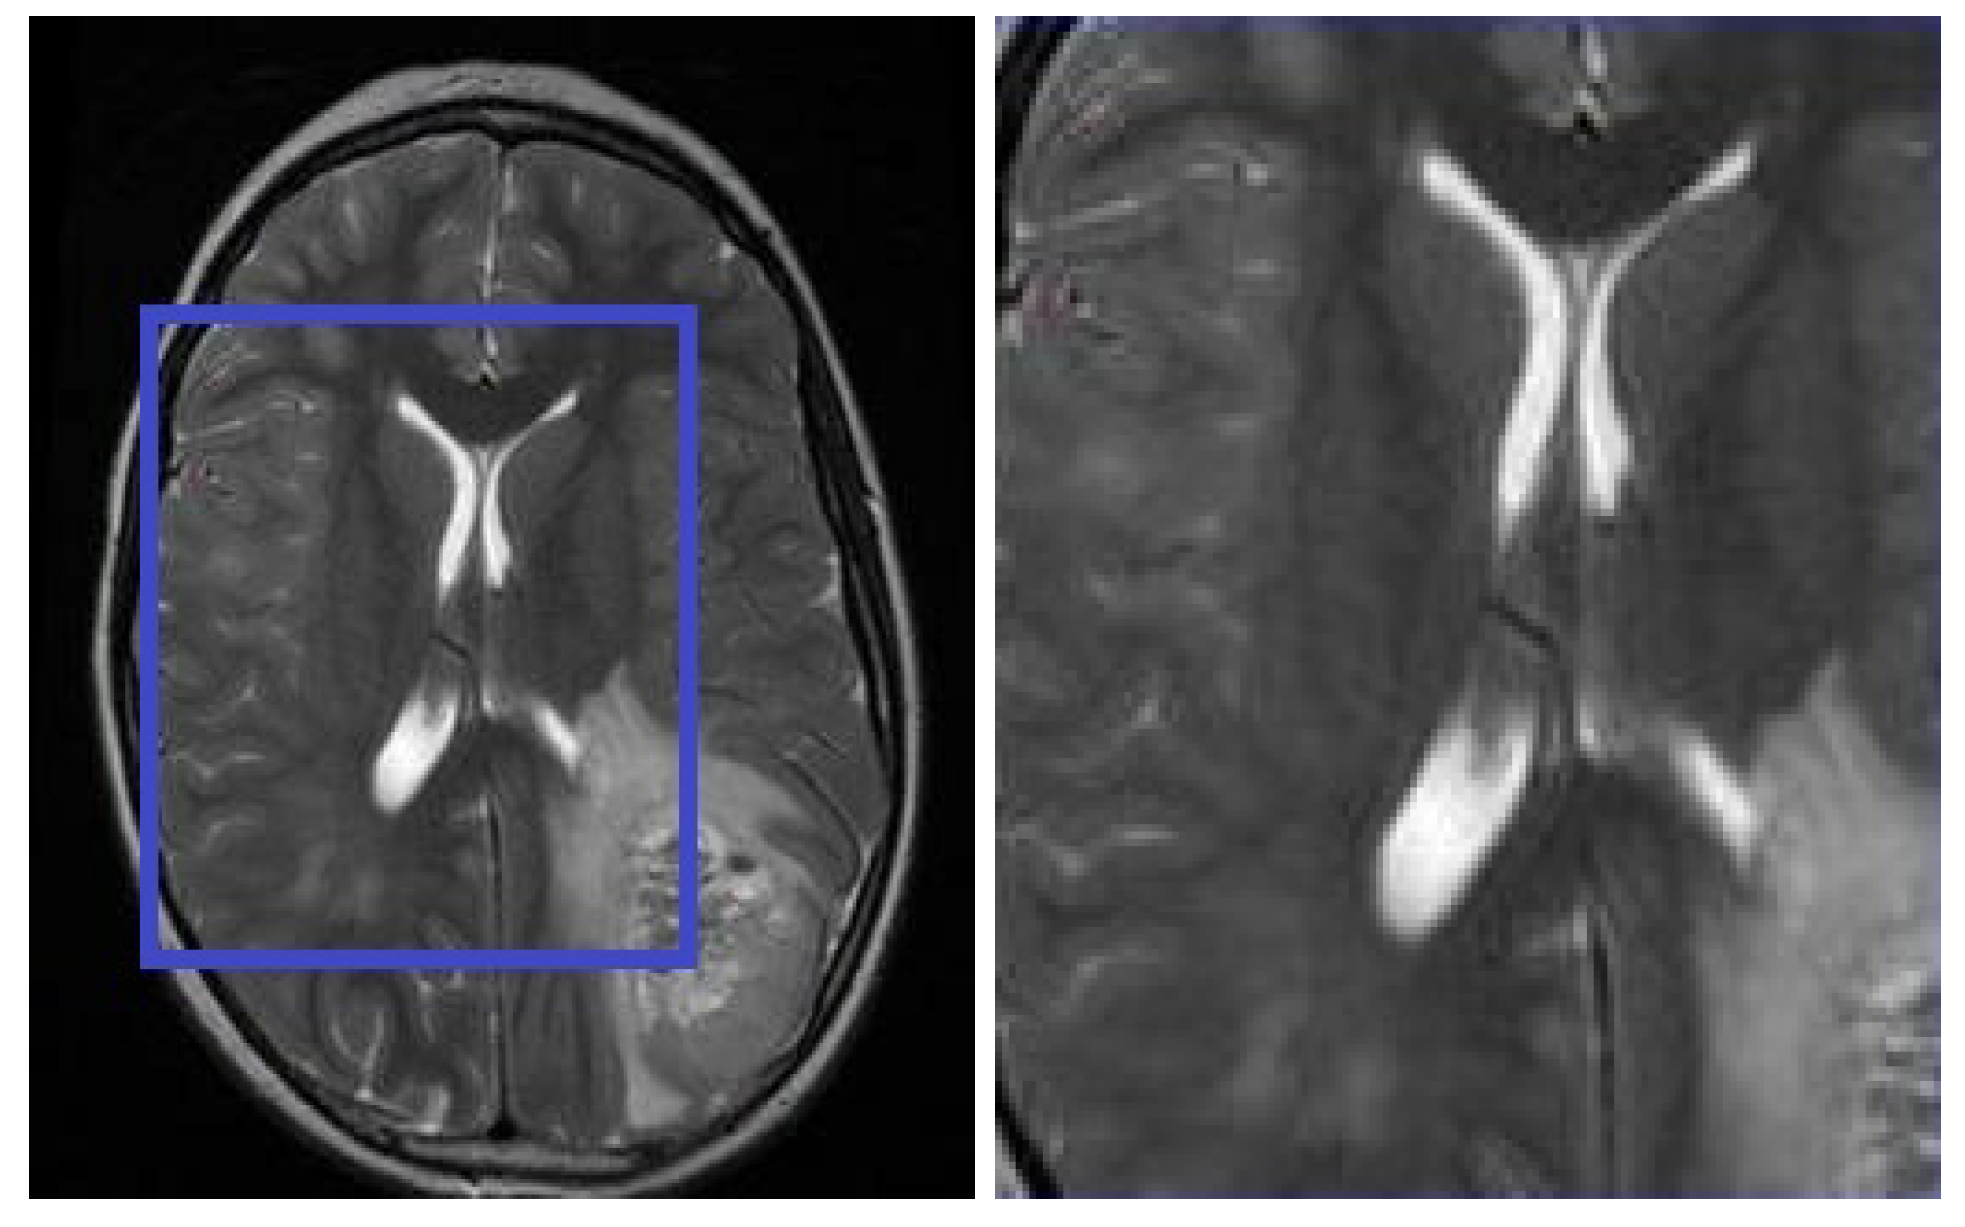

4.3. Subjective Evaluation